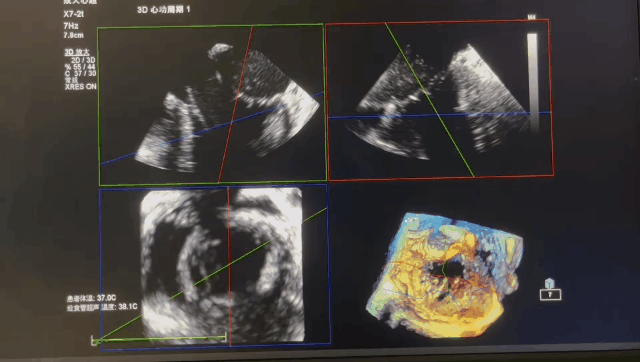

术后